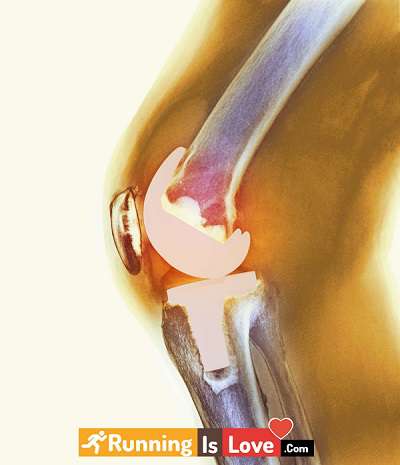

7.تعویض زانو

جراحی تعویض زانو برای جایگزینی بخش فرسوده زانو می باشد که با یک اتصال جدید که از فلز یا پلاستیک ساخته شده است، جایگزین می شود. تعویض زانو یکی از رایج ترین جراحی ها برای درمان آرتروز شدید می باشد.